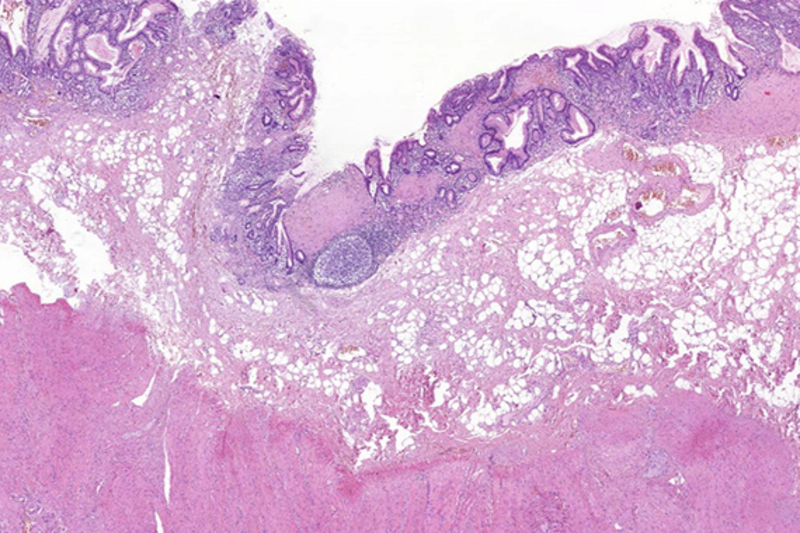

Histologically, lamina propria of gastric mucosa was expanded with amorphous paucicellular stromal deposits with cracking artifacts (Panels A and B). These depositions stained red with Congo Red stain (Panel C) and demonstrated characteristic apple-green birefringence in polarized light (Panel D). No malignancy was observed. Consequently, the final diagnosis was gastric amyloidosis.

Due to recurrent gastrointestinal bleeding and significant involvement of the stomach with amyloidosis, a distal resection of stomach was performed. Histological findings (Panel E) in the resection specimen, including Congo Red stain (Panel F) were similar to those described in the pre-operative biopsy.